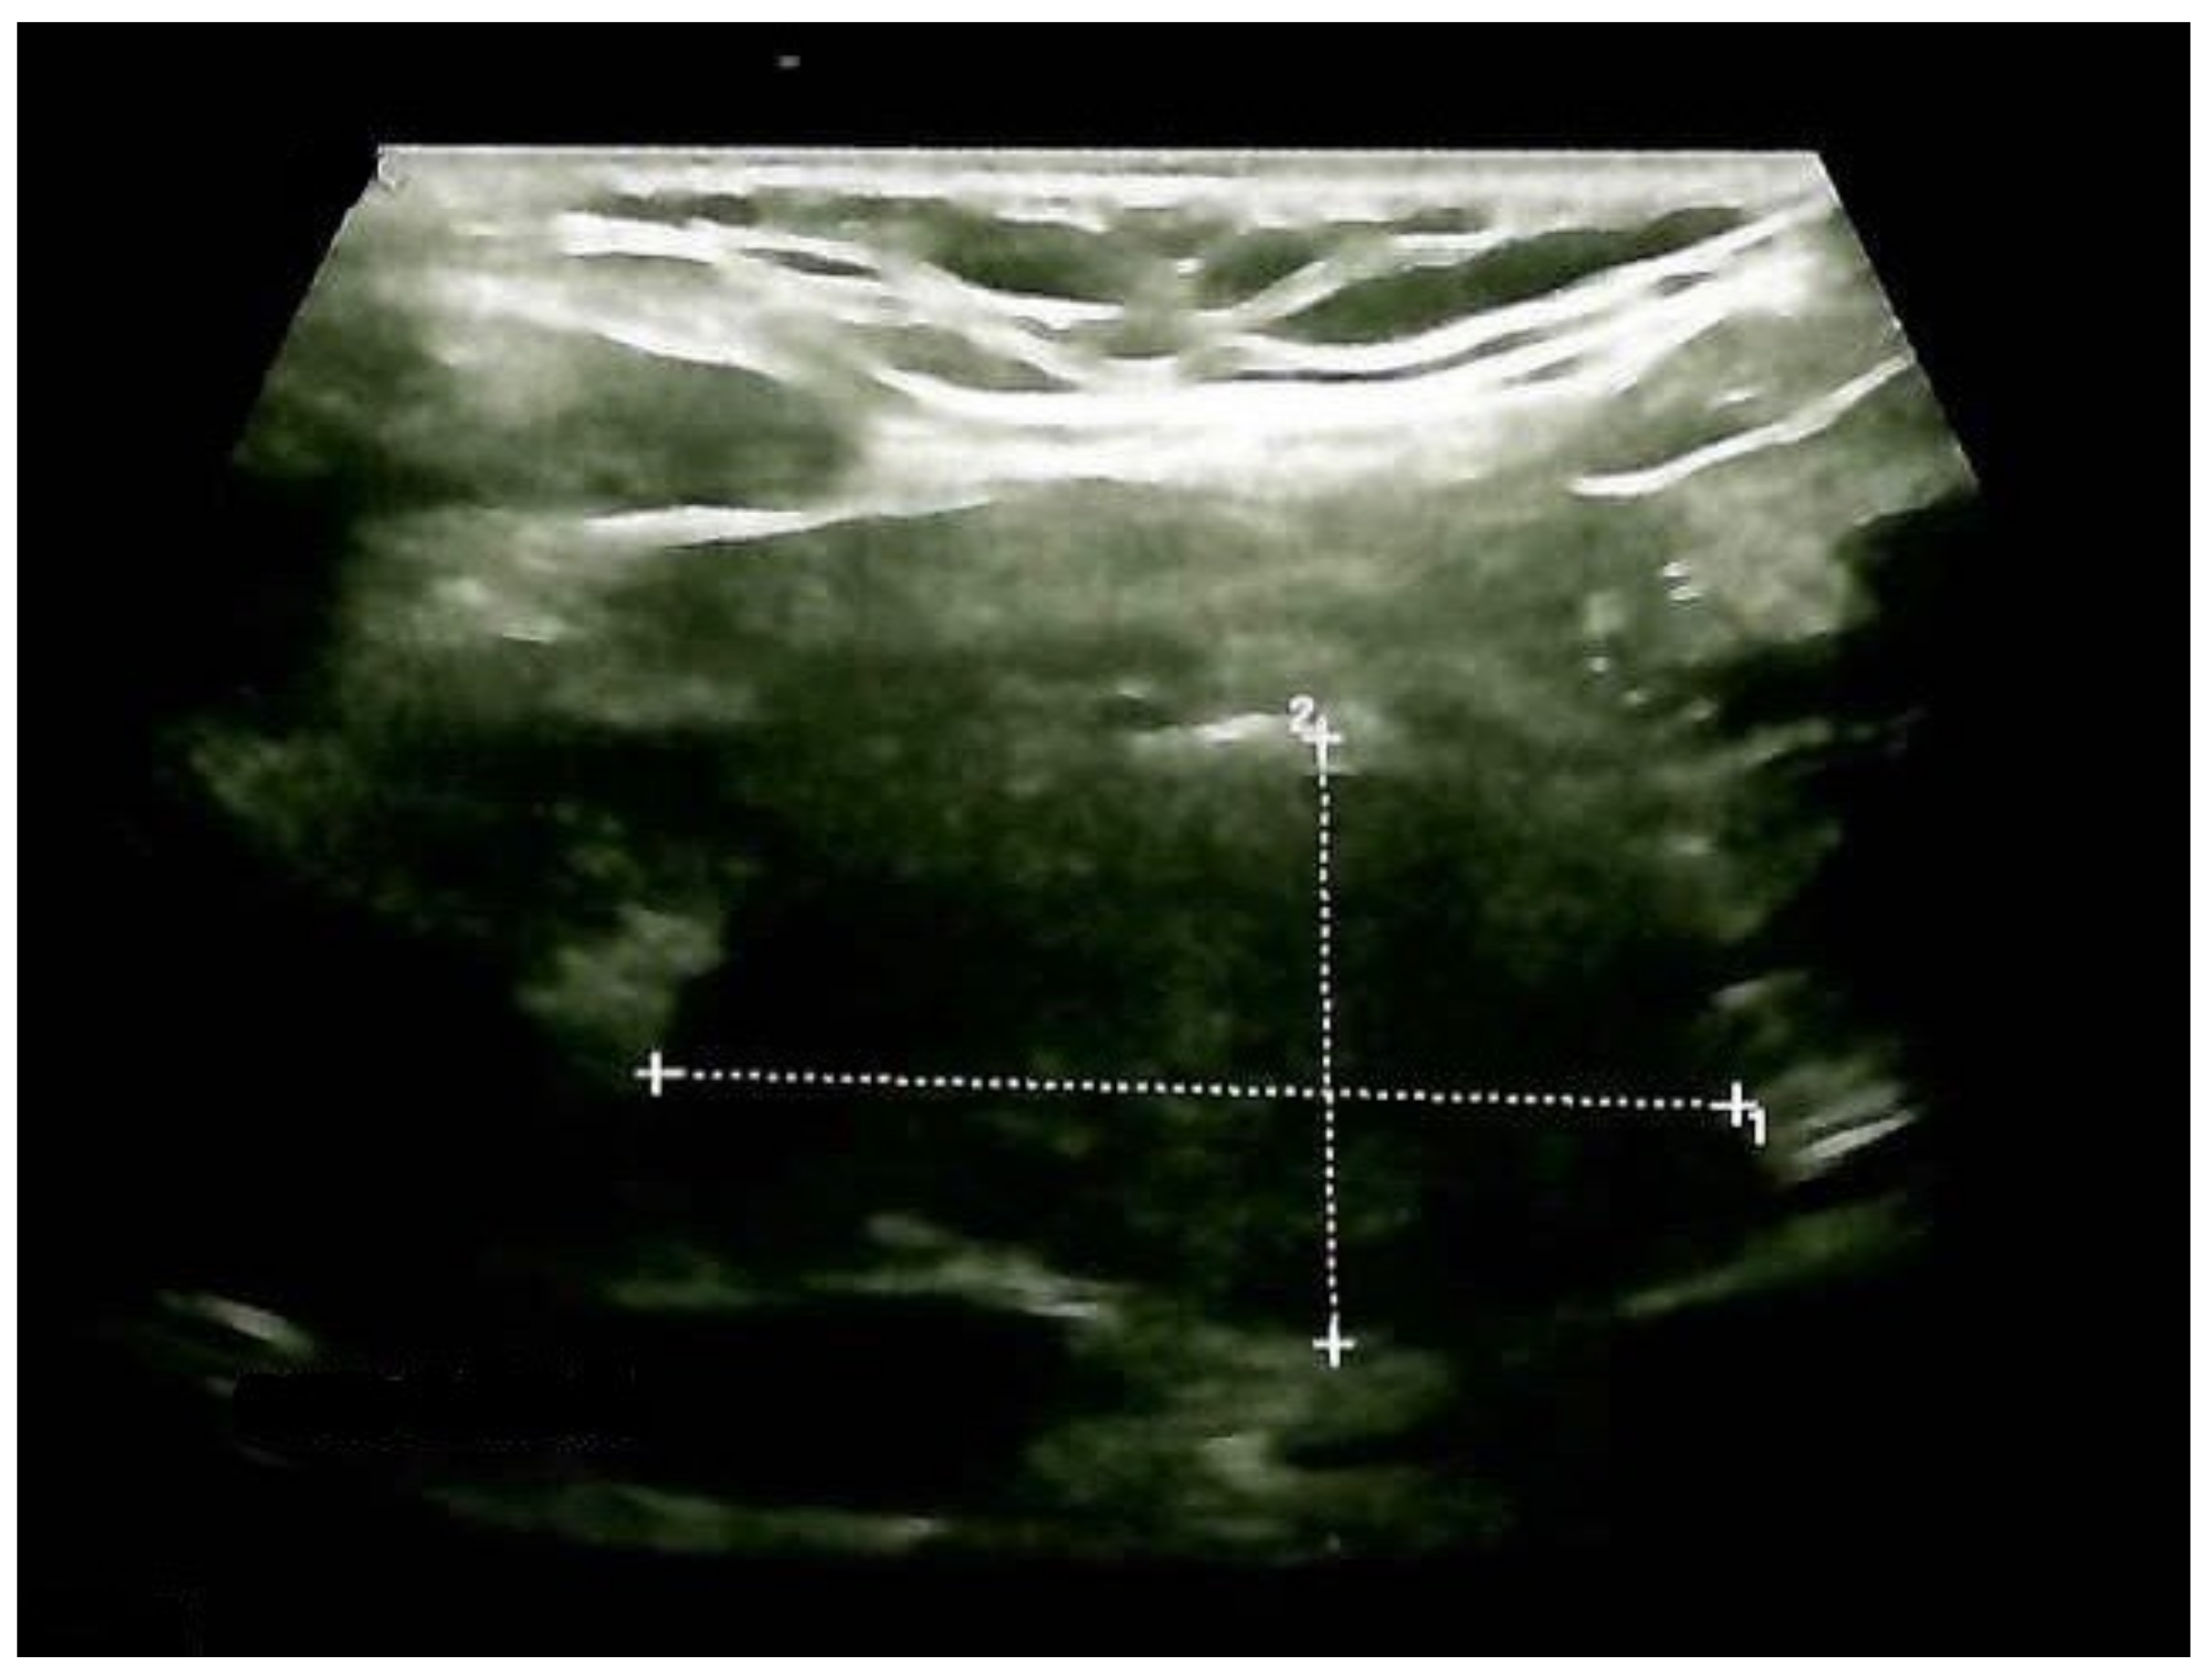

Thyroid ultrasound confirmed previous aspects in terms of gland enlargement and a multinodular goiter with a small increase in the largest nodule diameter. The right lobe was 2 by 2 by 4.3 cm, and the left lobe was 1.8 by 1.9 by 3.8 cm, with a hypoechoic, intensely inhomogeneous pattern; the lower half of the right thyroid lobe had a nodular conglomerate of 3.1 by 1.6 by 1.7 cm. Inferior to the right thyroid lobe, a hypoechoic mass with a structure similar to that of the thyroid of 3.66 by 2 by 2.6 cm was observed (ETTM). She had no neck lymph node involvement (Figure 5).

Figure 5.

Anterior neck ultrasound: hypoechoic mass (ETTM) extending from the right thyroid lobe, with a structure similar to the thyroid and pre-tracheal extension of 3.66 by 2 by 2.6 cm (longitudinal plane).